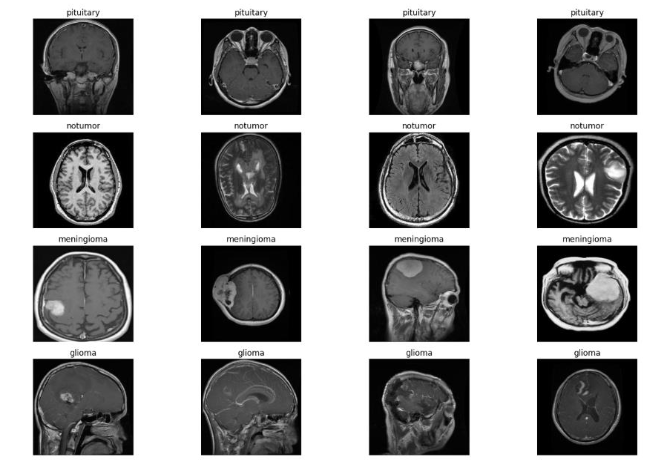

The experiments were conducted using a publicly available brain tumor MRI dataset consisting of three tumor categories glioma, meningioma, and pituitary tumor along with a non-tumorous (normal) class. Each image is a T1-weighted contrast-enhanced MRI slice stored in JPEG format.

As shown in Figure 2, the training dataset distribution illustrates a moderate class imbalance, with glioma and meningioma categories slightly overrepresented compared to pituitary and normal classes. This imbalance was later addressed through data augmentation and, where necessary, oversampling techniques to ensure that each class contributed equally to model learning.

The data presented in Figure 2 illustrates the raw input data. The four MRI modalities provide complementary information about the distribution of the four classes of Brain tumor.